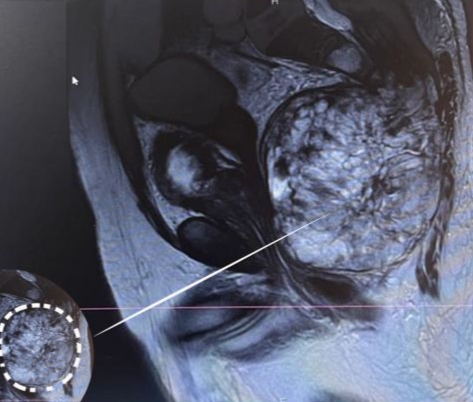

إنجاز طبّي جديد أضافته مستشفى خلف الحبتور في بلدة حرار العكّارية شمالي لبنان إلى سجلّها، إذ تم استئصال ورم نادر وضخم من أسفل العمود الفقري مع انتشار الورم نحو الأوعية والأعضاء الحيويّة في أسفل البطن.

أجريت العمليّة بنجاح تامّ مع استئصال الورم بشكل كامل، وكانت زنته نحو 1600غ.